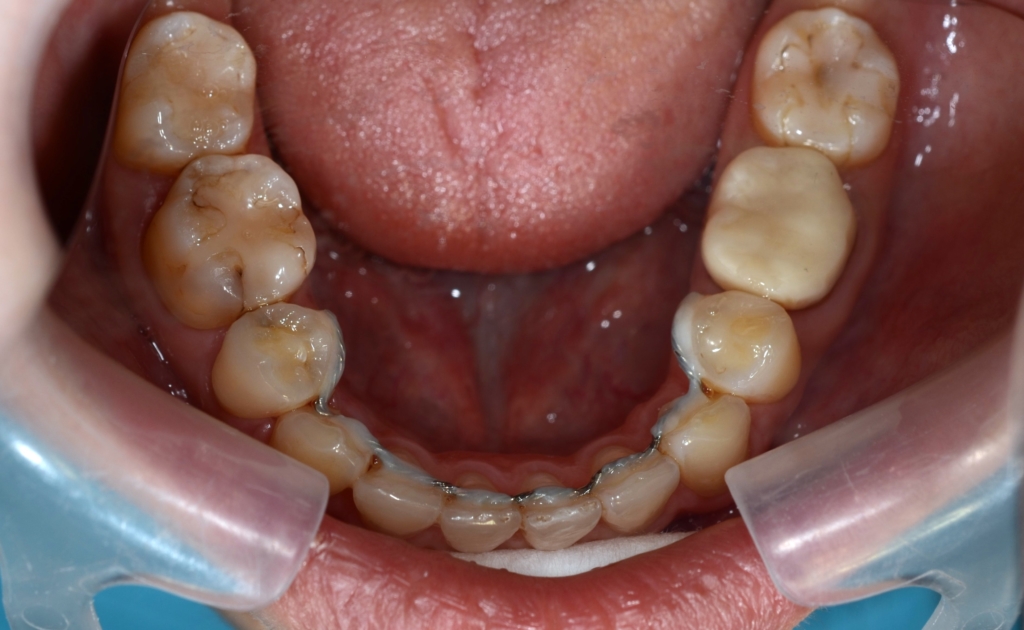

【After】

変な悪目立ちをするものはありません

矯正後の状態をレントゲン写真で確認すると、

【保定】 上下ともフィックスタイプ&クリアリテーナー

【治療期間】 3年6か月間

【治療費用】 87万6千円

【治療装置】 スタンダードtypeのマルチブラケットシステム、

アンカースクリューを計6本

PLAS & パラタルバー